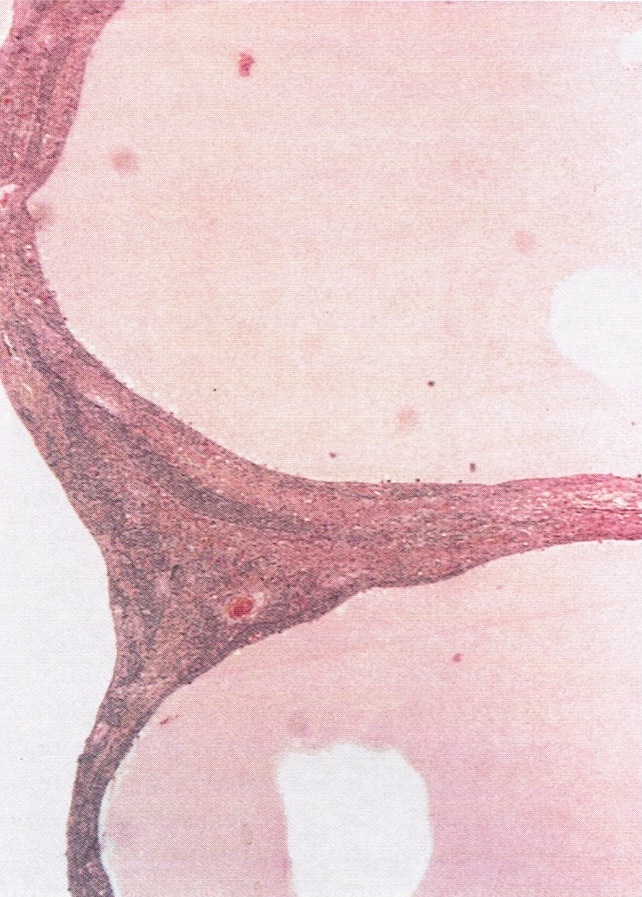

- Various patterns, including diffuse (the most common), trabecular and corded, insular, microfollicular (resembling Call-Exner bodies of the Graafian follicles: small follicle-like structures filled with eosinophilic material) and macrofollicular (the least common)

- Predominantly cystic granulosa cell tumor or macrofollicular pattern may mimic ovarian follicle

Microscopic (histologic) images

Contributed by Shabnam Zarei, M.D. and Sharon Bihlmeyer, M.D.

AFIP images